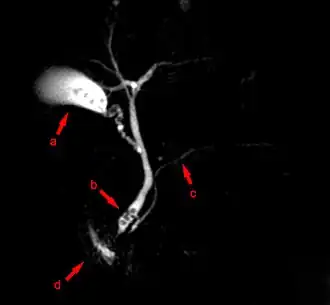

При исследовании печени, поджелудочной железы и жёлчных протоков ведущую роль занимают ультразвуковые исследования (УЗИ), компьютерная томография (КТ) и магнитно-резонансная томография (МРТ). При диагностике состояния пищевода распространено рентгеновское исследование с барием, при котором прохождение глотков бариевой взвеси регистрируется флюороскопически в реальном масштабе времени. Рентгенография пищевода применяется для выявления грыж пищеводного отверстия диафрагмы, опухолей, дивертикулов, стриктур, варикозного расширения вен, инородных тел. Рентгенография или рентгеноскопия с двойным контрастированием или без него применяется при исследовании желудка и двенадцатиперстной кишки с целью выявления язв, опухолей, стриктур, обтураций, контроля результатов оперативных вмешательств. Для диагностики опухолей кишечника, воспалительных заболеваний, причин непроходимости кишки, стриктур, обструкции применяется контрастная рентгенография, компьютерная или магнито-резонансная томография[28].

МРТ-изображение содержащих камни жёлчного пузыря и протоков